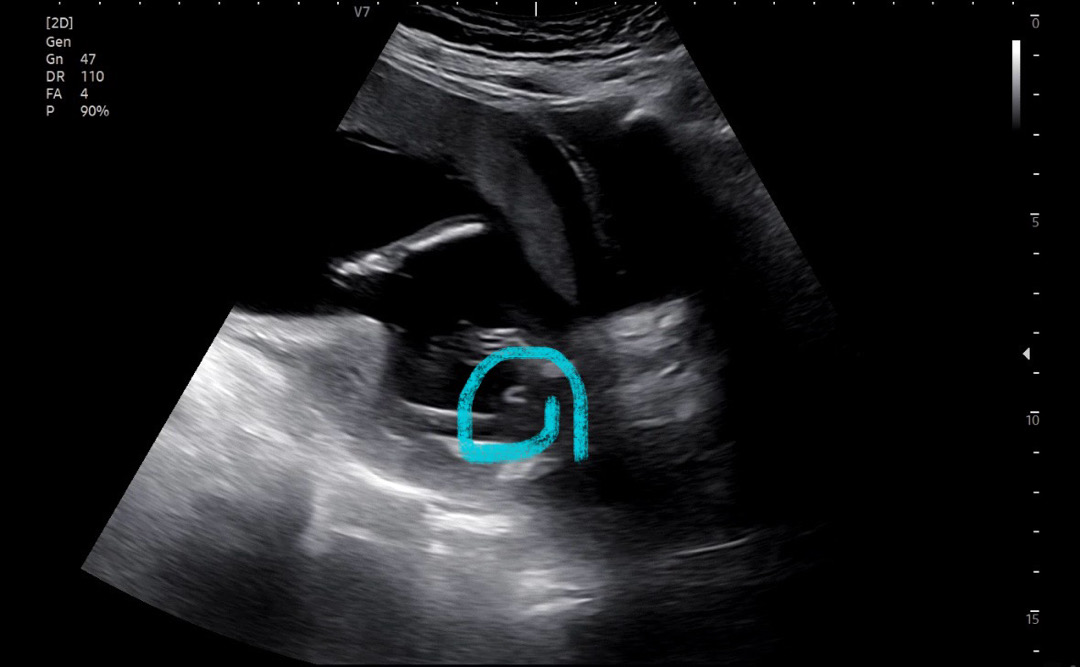

17주 성별 봐주실 분!!!

아기가 자꾸 움직여서 확실하게는 안 보이고 아마 아들인 것 같다고 했어요! 동그라미 친 게 그 부분인듯 한데 원래 저렇게 U자 모양인가요..?